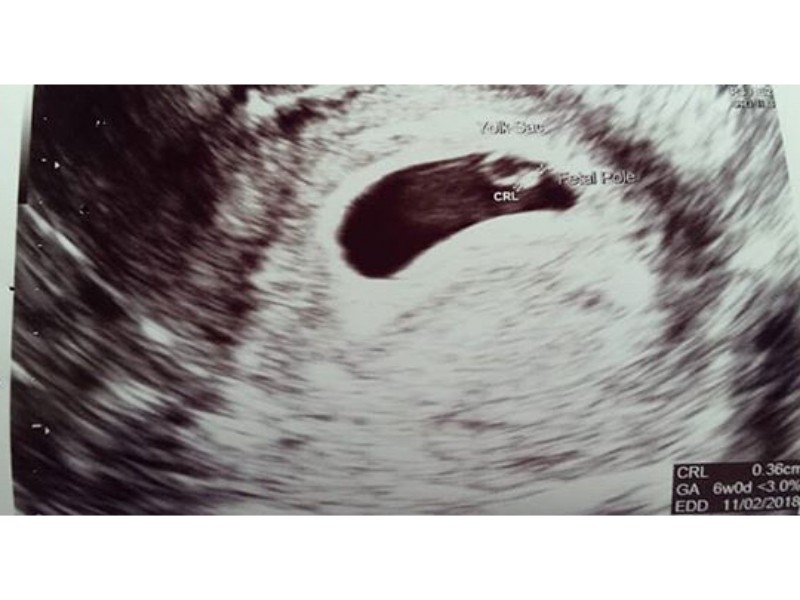

6. Hafta Gebelik Hafta Hafta Hamilelik Bayan Doktor

6. Hafta Gebelik Hafta Hafta Hamilelik Bayan Doktor From Pinterest